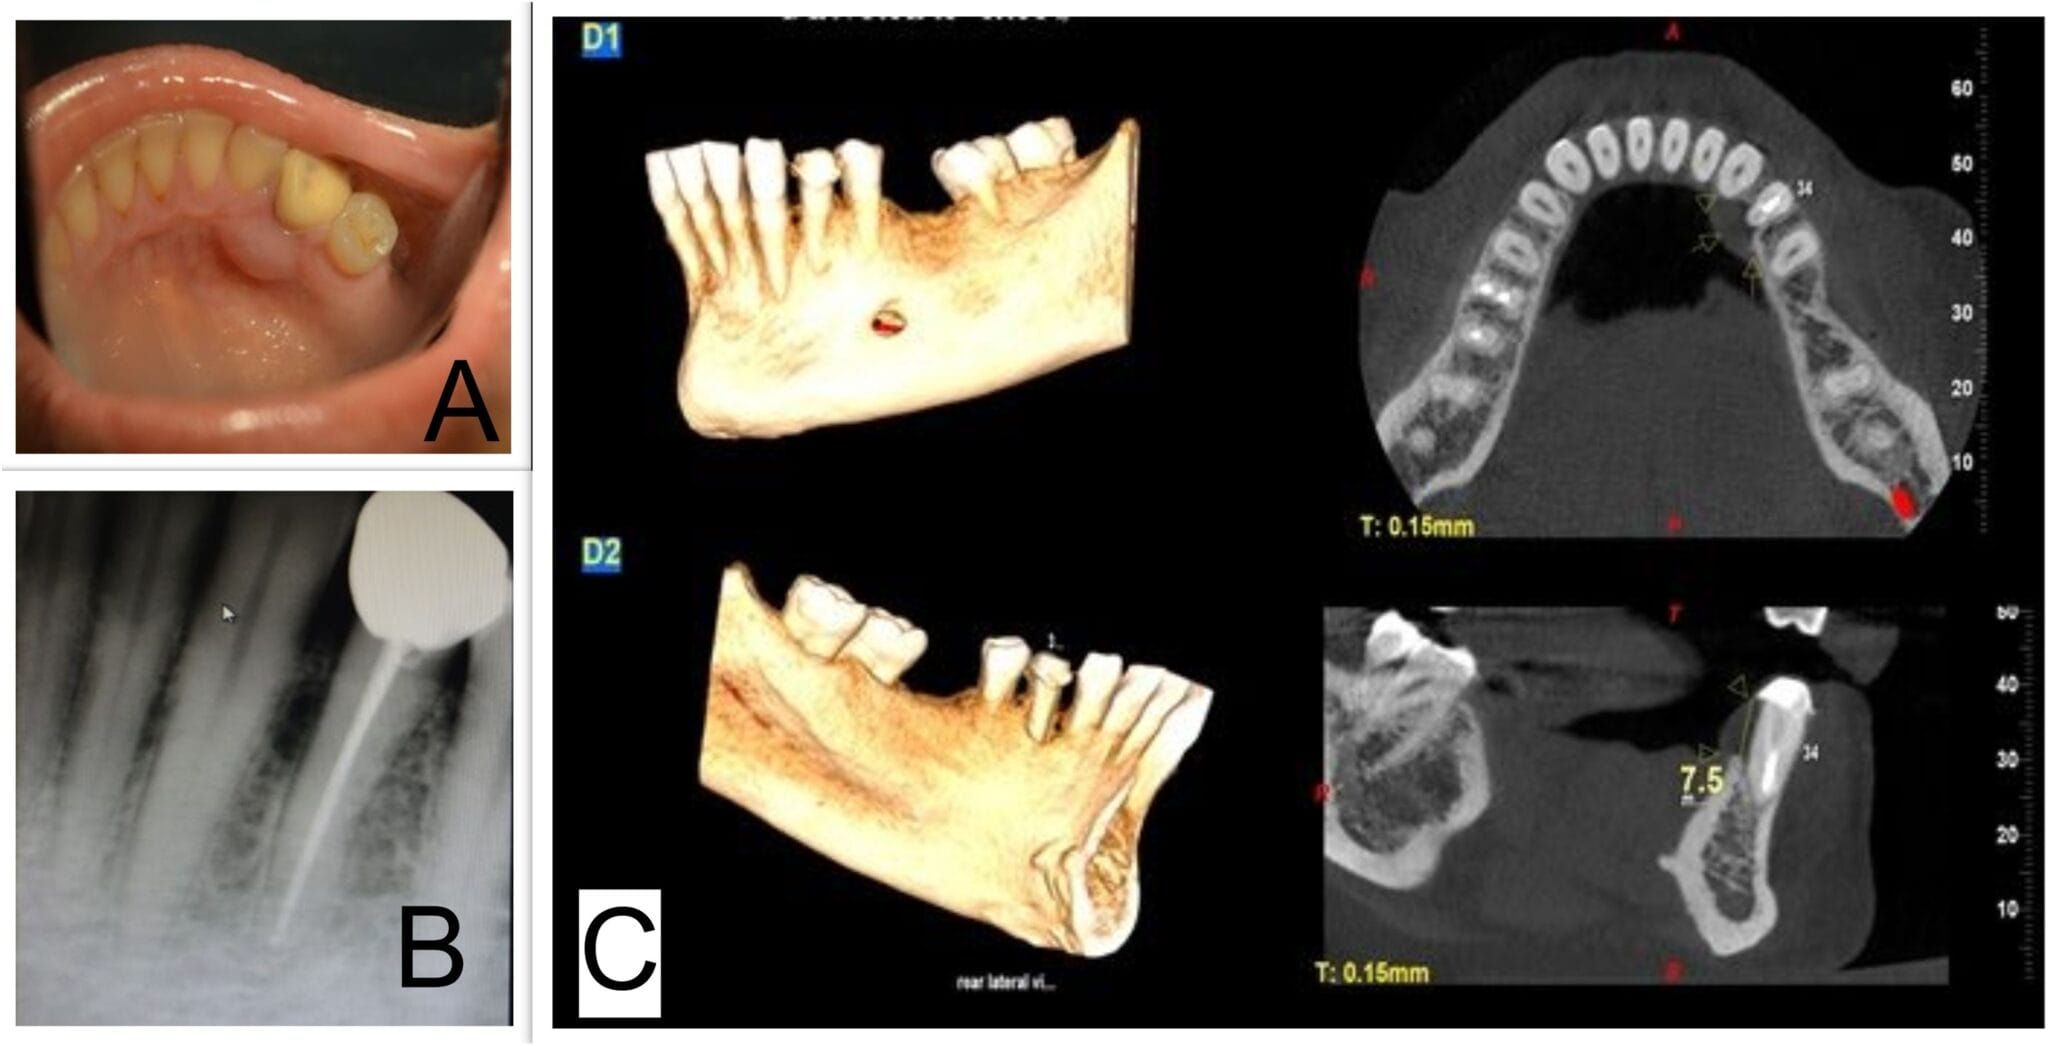

From thefuturedentistry.com

CYST AND CLASSIFICATION Focus Dentistry Are Dental Cysts Common A noticeable swelling or enlargement of the jaw or gums is a common symptom of odontogenic cysts. The condition can affect anyone, but. These cysts are sacs filled with fluid, tissue, or other substances and. Dentigerous cysts occur when fluid builds up over the top of a tooth that has not yet erupted. They form over the top of an. Are Dental Cysts Common.